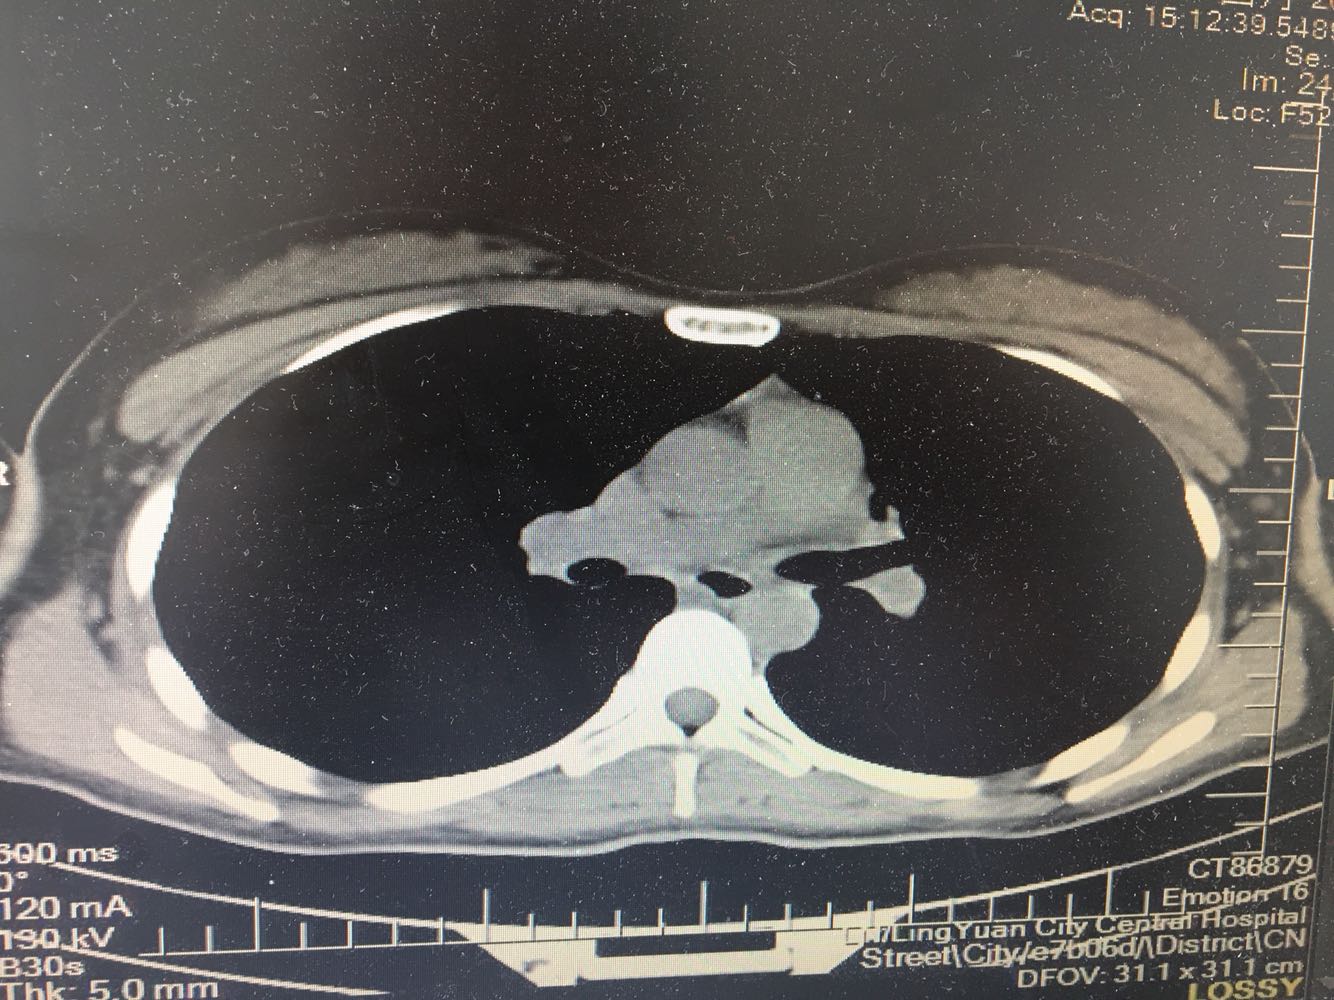

女,26岁,咳嗽1周,咳痰不畅,咽喉痒,口服阿莫西林无好转,昨日发热,体温38.5摄氏度,于门诊查肺CT后以肺炎收入院,病来无盗汗,无咳血,无消瘦及乏力,无头痛,无肢体酸痛,饮食睡眠可,二便正常

神清言明,咽部无充血,扁桃体不大,双肺呼吸音清,无罗音,服软无压痛。

支原体抗体1:160,结核抗体弱阳性。支原体肺炎个别可见上叶病变,该患无结核中毒症状,考虑支原体肺炎可能性大,但肺尖为结核好发部位,需要抗炎治疗后复查观察疗效。